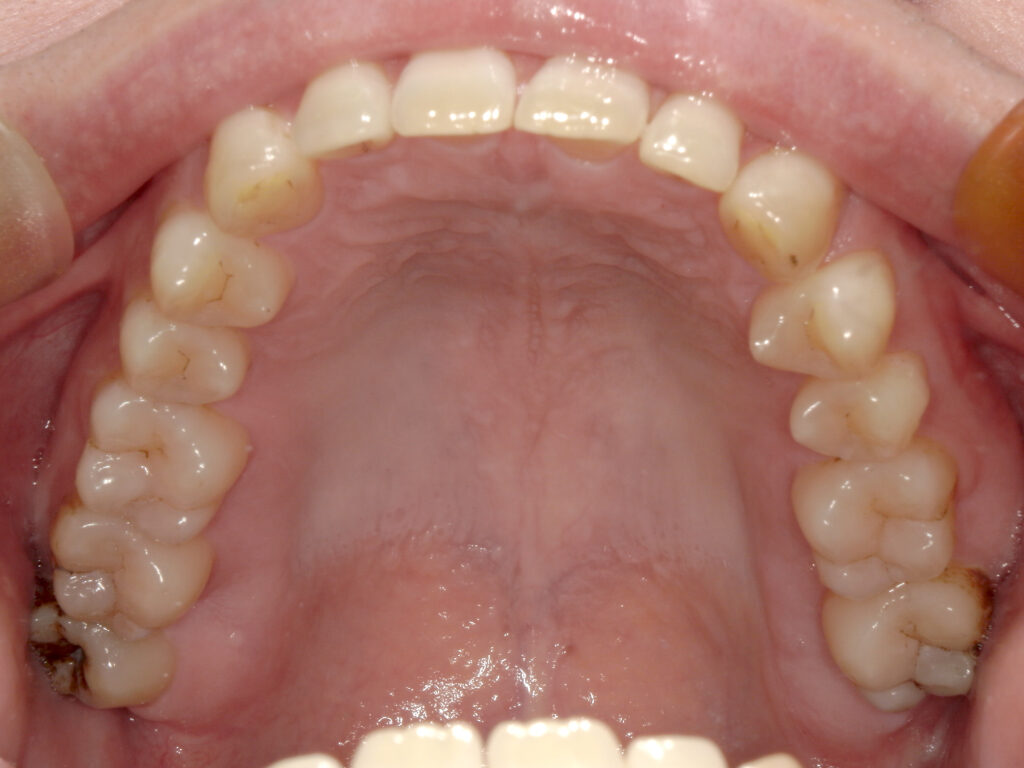

上顎

治療前

治療後

患者様は上下の横の前歯の隙間を気にされており、「できれば完全に隙間を閉じたいが、ある程度改善されればよい」とのご希望で来院された。 インビザライン矯正では、前歯の近接移動を中心に計画し、効率的に隙間を閉鎖するため犬歯・小臼歯にアタッチメントを付与。また、閉鎖後の歯肉退縮やブラックトライアングルを最小限に抑えるため、歯根の平行性を意識して移動を行った。 治療により上下前歯の隙間は良好に閉鎖し、咬合も安定。審美的な改善とともに、発音や清掃性の向上にもつながった。 |